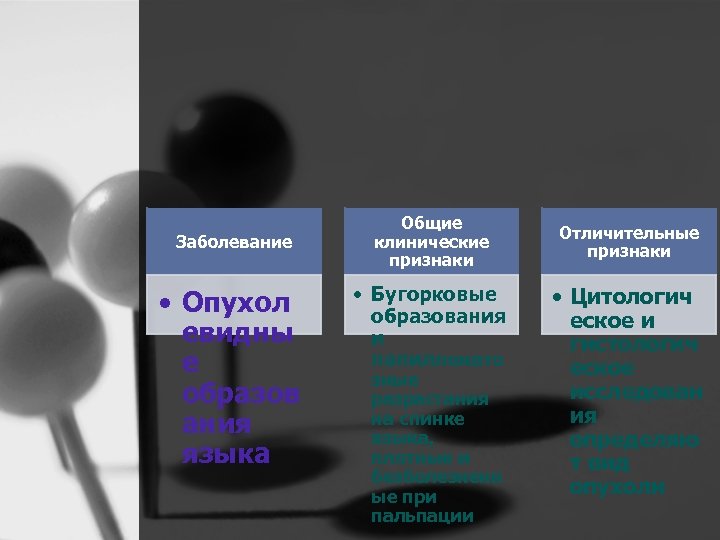

Заболевание • Опухол евидны е образов ания языка Общие клинические признаки • Бугорковые образования и папилломато зные разрастания на спинке языка, плотные и безболезненн ые при пальпации Отличительные признаки • Цитологич еское и гистологич еское исследован ия определяю т вид опухоли